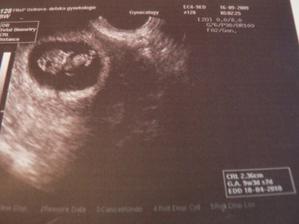

16.9.09 druhá fotečka našeho piškotka, dostáváme těhu průkazku 🙂